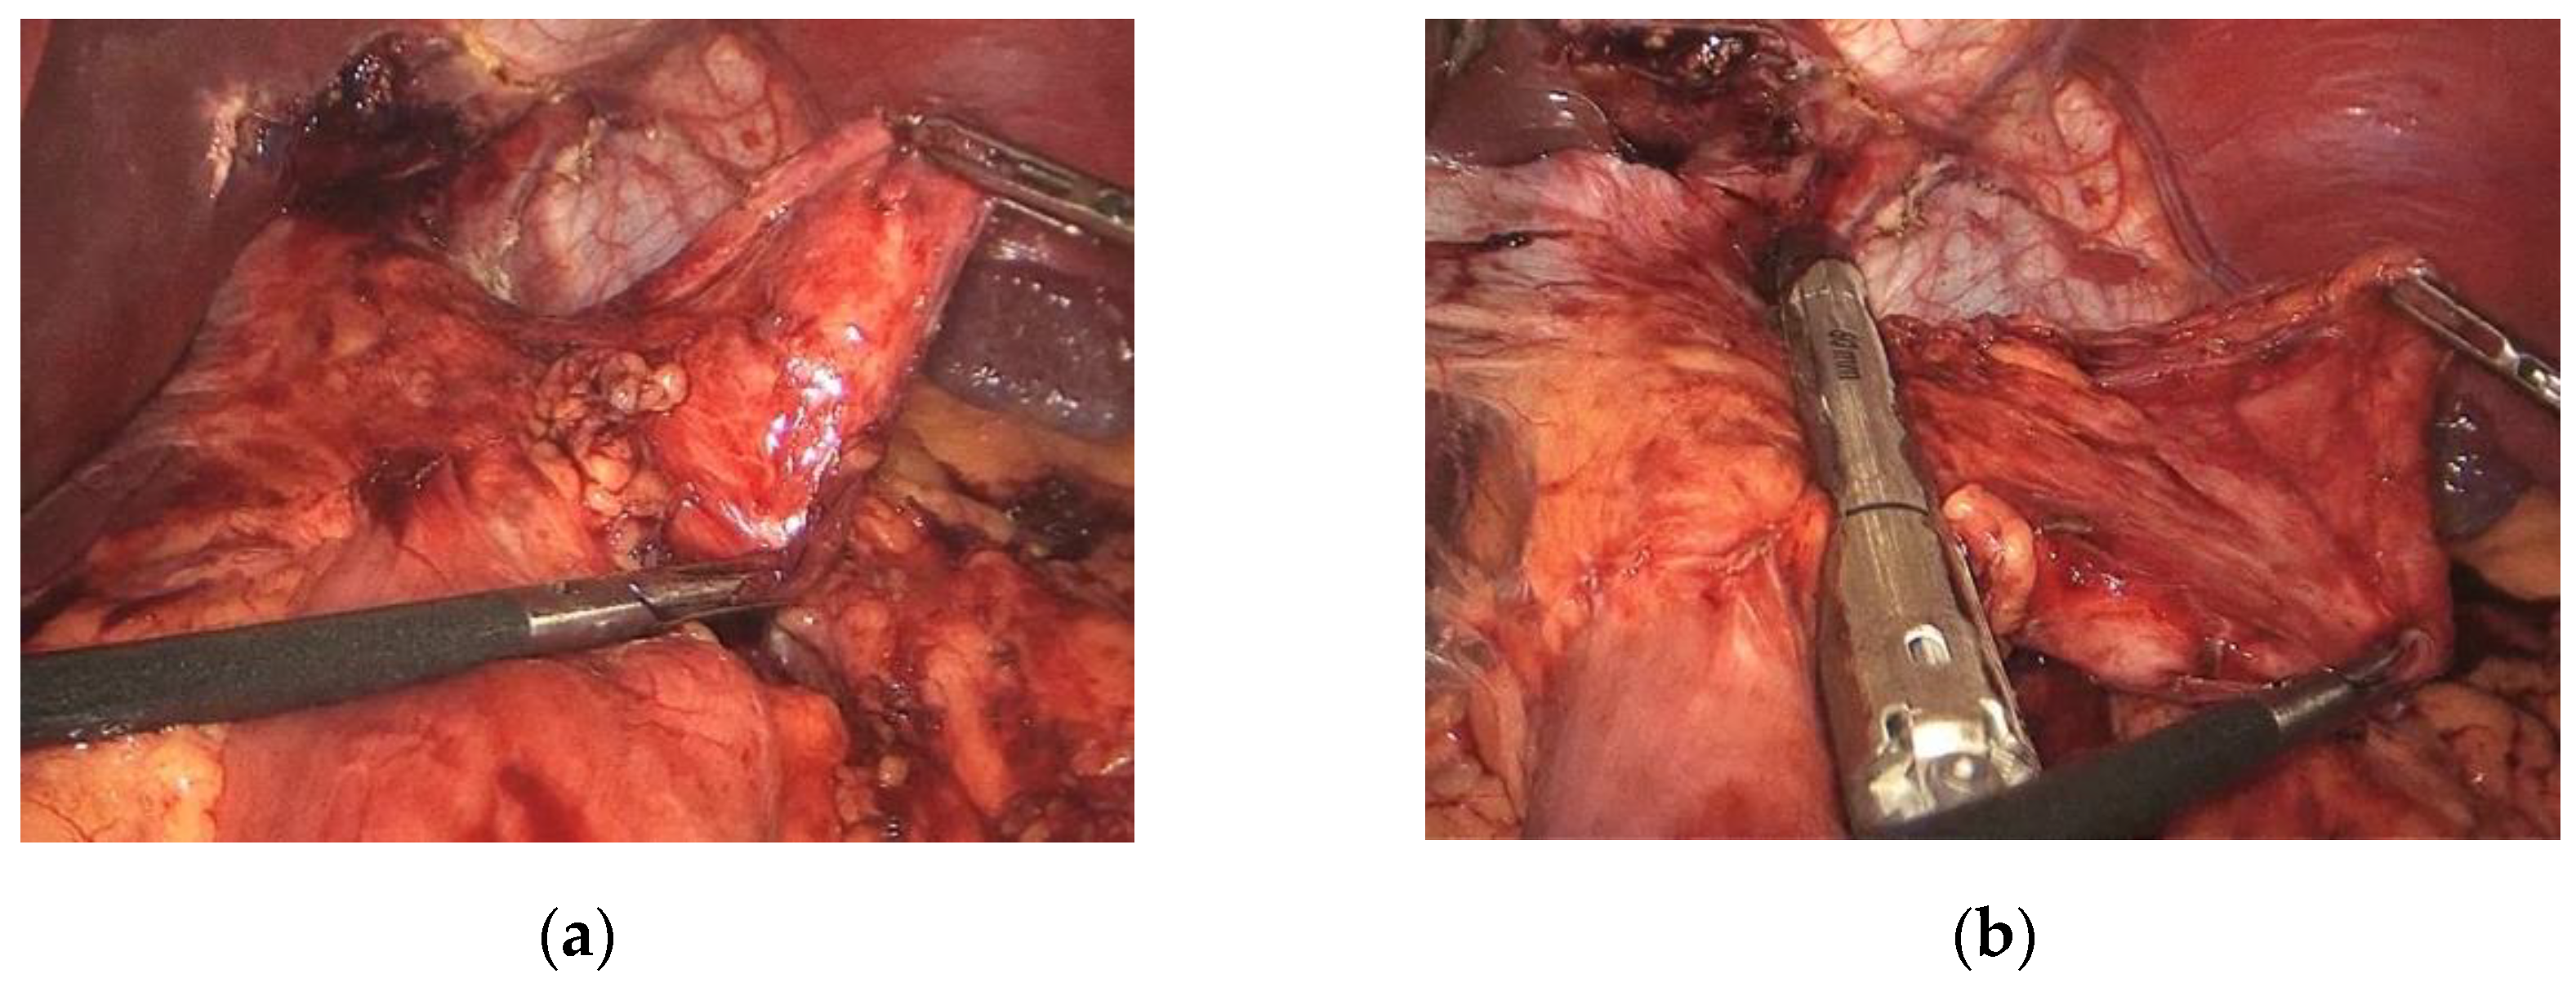

2.2. Surgical Technique